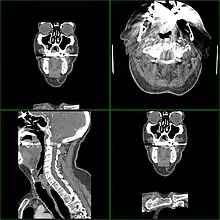

Guldtand absorberer røntgen i CT-scanner